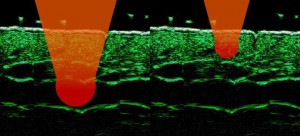

-Μέθοδοι θεραπείας υψηλής ενέργειας

(λέιζερ, RF-Ραδιοσυχνότητα, HIFU-Υψηλής Έντασης Εστιασμένος Υπέρηχος, κ.λπ.)